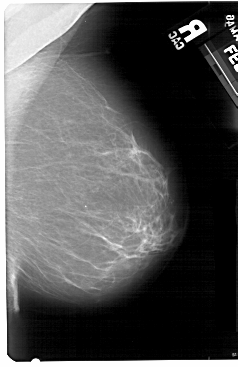

A_1493_1.LEFT_CC

LEFT_CC LINES 5491 PIXELS_PER_LINE 3121 BITS_PER_PIXEL 12 RESOLUTION 43.5 OVERLAY